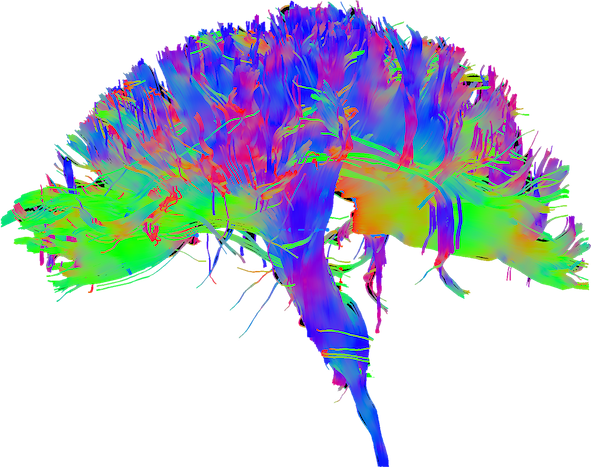

Hi. I’m Bimal. That’s my brain. It’s how I think through messy problems and build useful things.